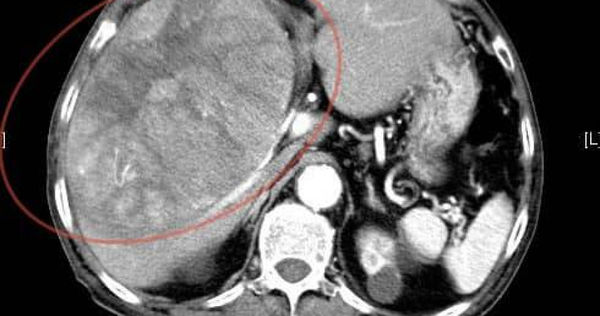

直到2個月前,阿公出現上腹疼痛及胃酸逆流,至錢政弘門診就醫。因右上腹壓痛明顯,初步懷疑是膽囊問題,安排腹部超音波檢查,結果竟發現肝臟有一顆高達15公分的腫瘤。進一步電腦斷層確認為晚期肝癌,無法開刀,治療後不久便不幸離世。